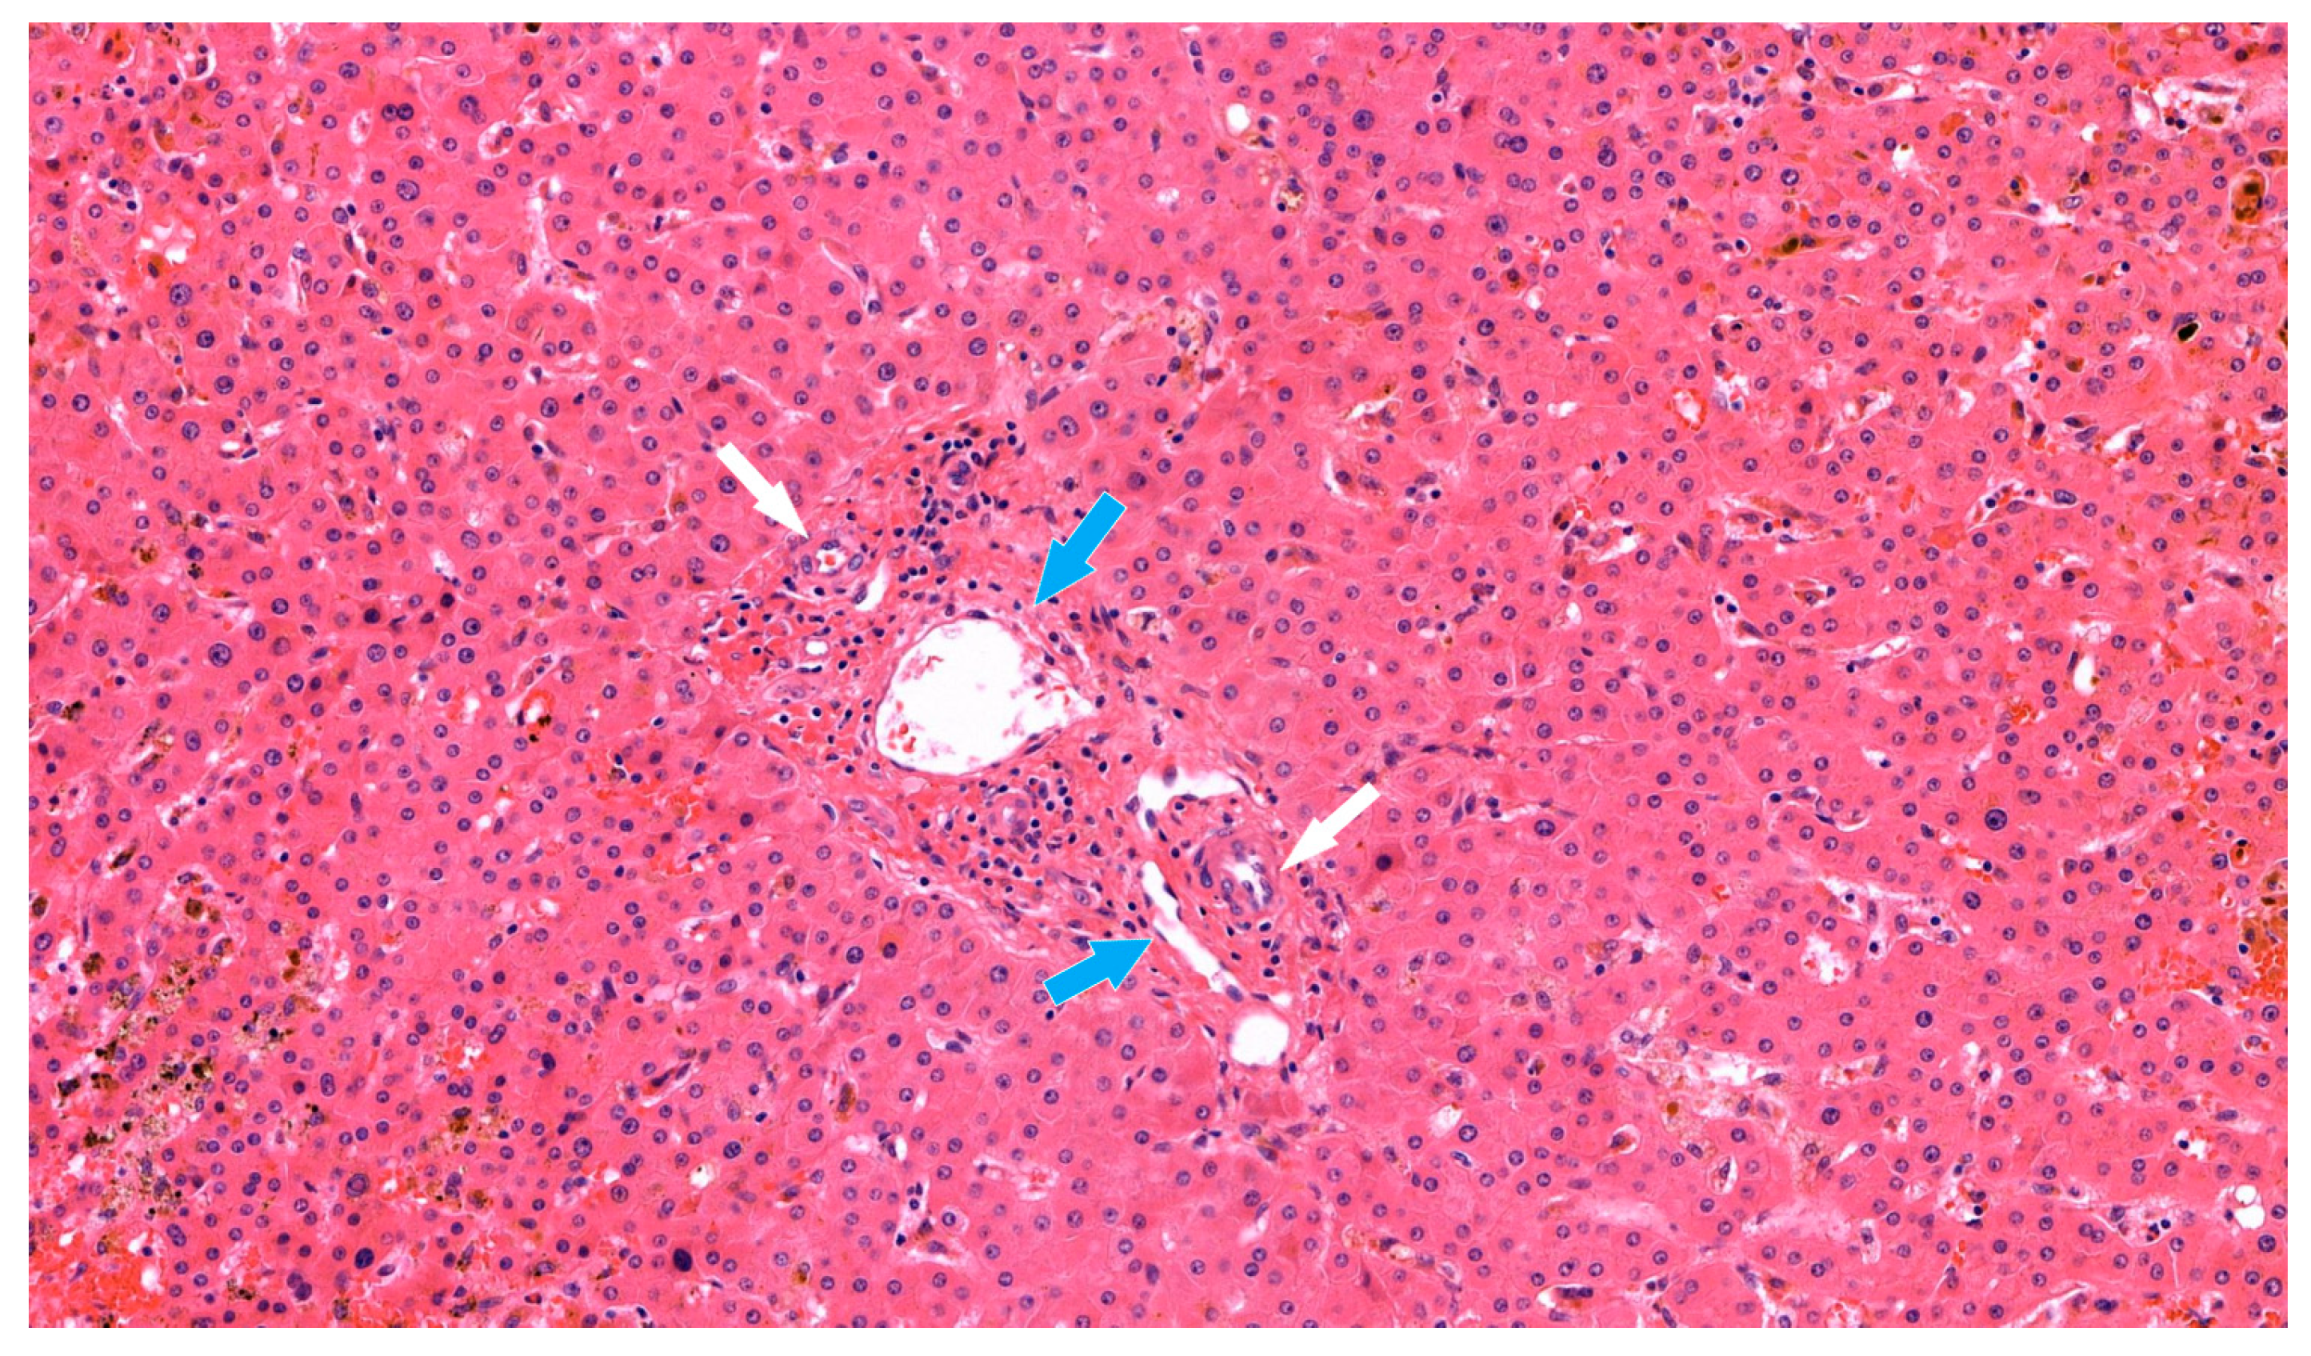

Despite such treatment, the serum total bilirubin level increased dramatically, up to 22.9 mg/dL. A liver biopsy was performed, and the pathologic findings showed biliary ductopenia suggestive of chronic rejection (Figure 2). Steroid pulse therapy and increased tacrolimus doses did not resolve the rejection. A humoral component of rejection could not be fully excluded, and so rituximab was administered as a rescue therapy in a single dose of 600 mg (375 mg/body surface area), which corresponding to 60 days prior to re-transplantation. All attempted treatments were ineffective.

Figure 2. The liver allograft biopsy suggestive of chronic rejection (HE stain, 170×). In the portal tract, inflammatory cells were observed around hepatic artery (white arrow) and portal vein (blue arrow). Loss of interlobular bile duct was apparent with marked canalicular cholestasis.